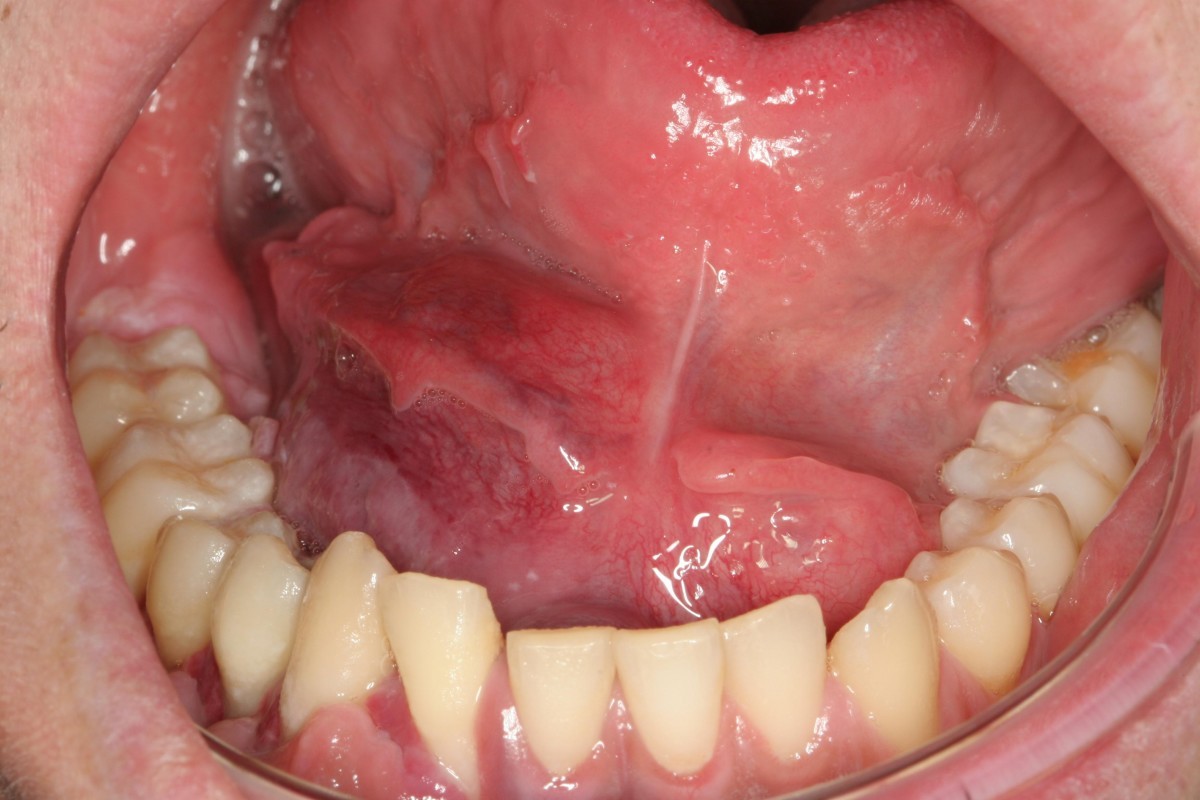

STOCK IMAGE, oral medicine submandibular gland swelling large lump under the tongue of a 28 year

From www.medicalimages.com

STOCK IMAGE, oral medicine submandibular gland swelling large lump under the tongue of a 28 year Abscess Under Tongue The most common cause of ludwig's angina is a tooth infection that spreads, although other conditions (including tongue piercings) can lead to strep and staph bacteria entering the tissue. Ludwig angina is a type of bacterial infection that occurs in the floor of the mouth, under the tongue. The swelling can be so severe that it cuts off the person’s. Abscess Under Tongue.